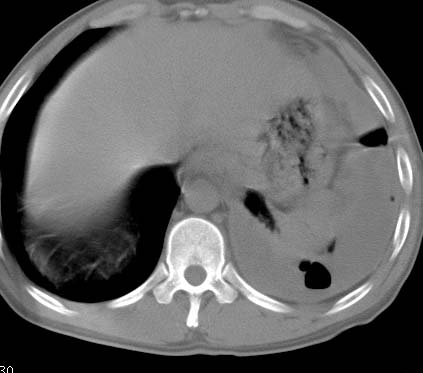

标题: CT10145:男性,30岁,活动后气促2月余.隔疝伴胸腔积液.右上肺结 [打印本页]

男性 病人 30岁,活动后气促2月余.隔疝伴胸腔积液.右上肺结核!

左侧胸腔积液,并胸腔内见多个含液 气组织,并相互重叠。影像特征很特殊,应该是“膈疝”。支持!

左侧膈疝,及左侧胸水,双上肺结核。